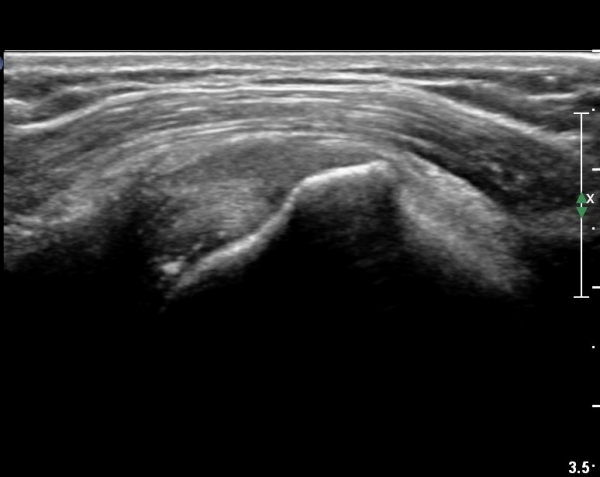

¿À±¸µ¹±â°ßºÀÀδë Á¾´Ü¸é°Ë»ç¿¡¼­ ƯÀÌ ¼Ò°ßÀ» º¸ÀÌÁö ¾ÊÀ¸³ª(»çÁø 1)